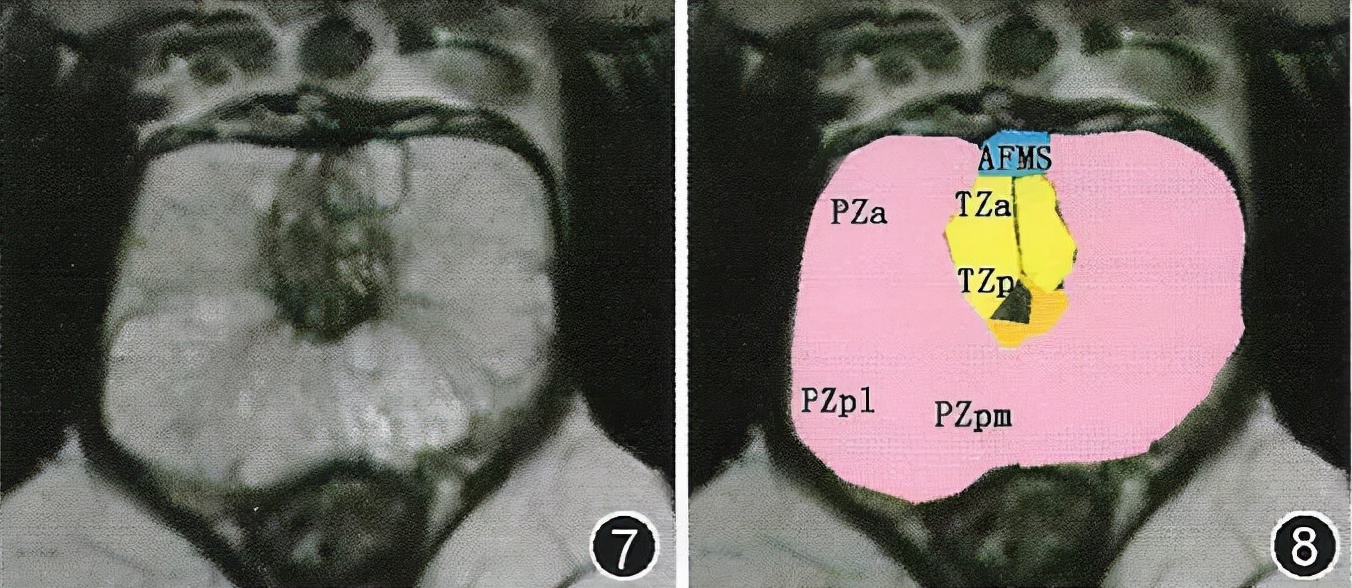

图7,8 前列腺中部解剖分区图 。图7为前列腺中部MR检查横断面T2WI。图8为示意图, 其中粉色为PZ, 包括PZa、PZ pm和PZpl; 黄色为TZ, 包括TZa和TZp; 橘色为尿道周围带; 深蓝色为AFMS